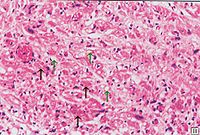

心脏细胞病变组织

克山病的主要病变是心肌实质的变性、

坏死和纤维化交织在一起心脏呈肌原性普遍扩张,心壁通常不增厚。20%的患者可见附壁血栓及肺、脑、肾、末梢血管的栓塞。光镜可见心肌变性和坏死。心肌变形呈弥漫性,坏死呈灶状分布。病变通常以左心室室间隔部为重,右心室较轻。点镜主要表现为线粒性肿胀、增生和嵴及肌原纤维破坏。